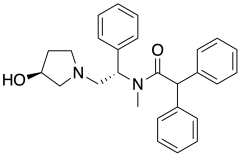

Biased ligands

Receptor heteromer targeting ligands

Uncategorized opioids

Structures

| Uncategorized opioids | ||||

|---|---|---|---|---|

|

|

| ||

|

|

| ||

|

Nalodeine Nalodeine |

|

| |

|

||||